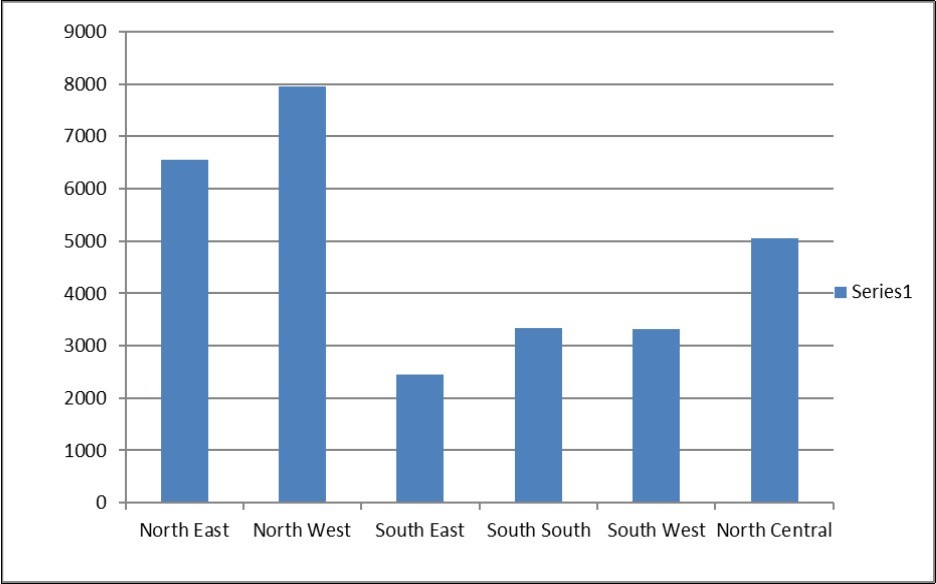

On geo-political zones basis (Figure 2), the North West has the highest mortality rate, followed by the North East, North Central, South South, South West and with South East carrying the least. The reason for these differences is that we have higher proportion of children in the Northern zones who have never received vitamin A supplements and immunization. Also breastfeeding rate in these zones is lower than in the Southern zones, as is the proportion of children who received complementary feeding. Use of un-iodized salt is also more common in the Northern part of Nigeria. Identifiable causes of death in these area are diseases like Malaria, Vaccine preventable diseases particularly measles, pneumonia, diarrhea, and Neonatal Jaundice. Increased in prices of food and poor households became more and more food insecure. The most food insecure households were located in the Northern region where the childhood mortality indices were also high. Children in poor Nigerian households are chronically undernourished, suffering a recurrent lack of access to food of sufficient quality and quantity, good healthcare, and necessary caring practices.

Figure 2.Data Analysis-Distribution by Geopolitical Zones